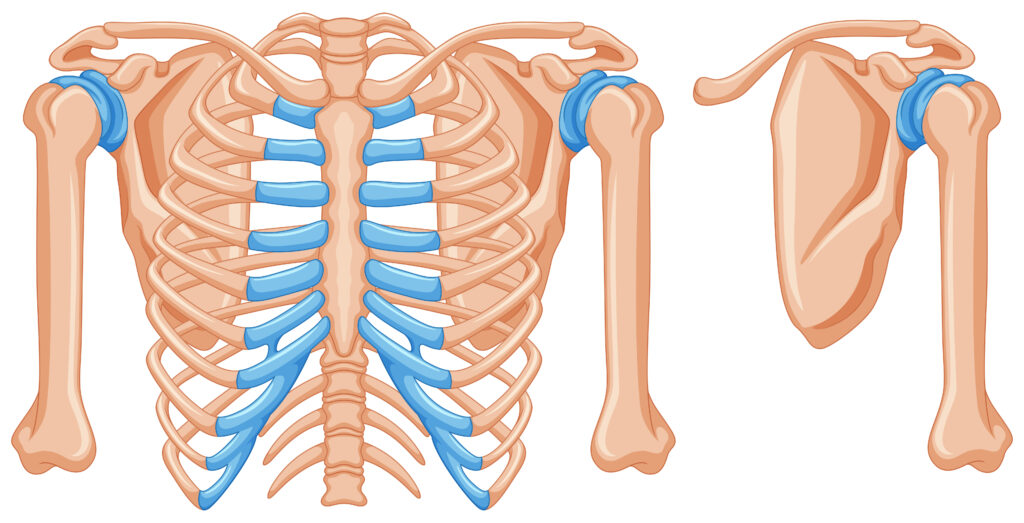

まず胸郭とは、肋骨・胸椎・胸骨で構成される上半身の骨格のことを指します。胸郭は本来、呼吸に合わせて広がったり閉じたりしながら、体幹の動きにも関わっています。

また、背骨の中でも胸椎(胸の背骨)は回旋(ひねり)や伸展(反る動き)を担う重要な部分です。

しかし、デスクワークやスマホの使用、猫背姿勢が続くと胸郭周りの筋肉が硬くなり、肋骨や胸椎の動きが悪くなります。すると本来胸郭が担うべき動きが失われ、体を反らす・ひねるといった動作を腰が代わりに行うようになります。

腰椎(腰の背骨)は、実は構造的に大きくひねる動きが得意ではありません。

それにもかかわらず、胸郭が動かないことで腰が無理に動くと、椎間関節や周囲の筋肉に負担がかかりやすくなります。これが慢性的な腰痛につながる原因の一つです。